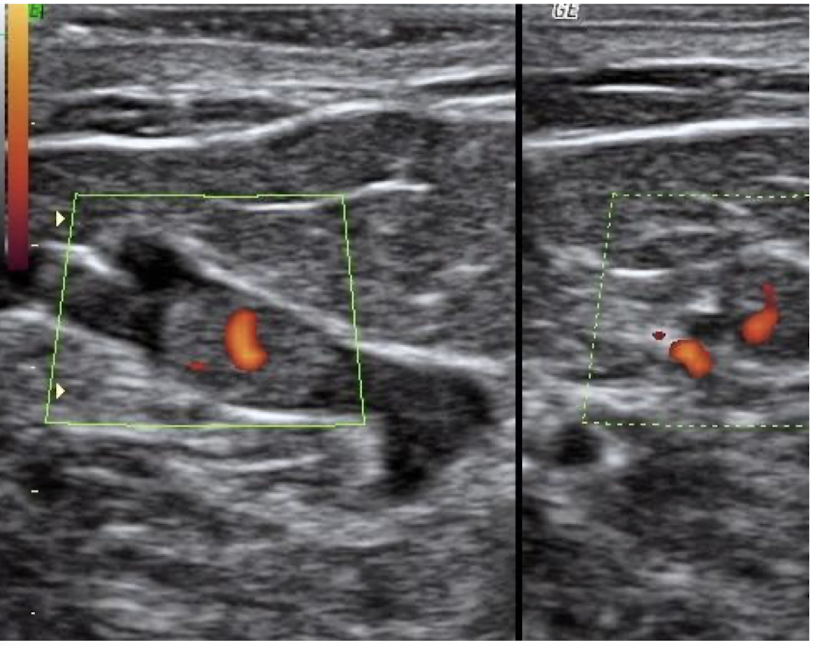

intraductal papilloma

small tumor that grows within the acini of the breast and projects from the lumen of the duct via a vascular stalk

s/s: intraductal papilloma

spontaneous nipple discharge (serous or bloody)